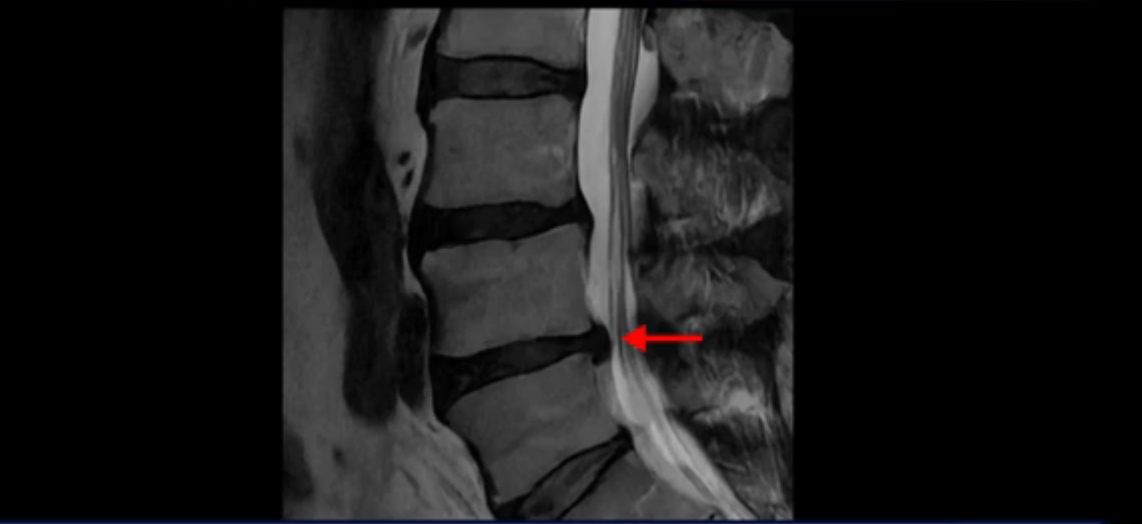

이분 MRI를 잠깐 보실까요? 보시면 두 마디가 특히 안 좋은데 3번 4번 디스크가 터져서 흘러 내려 있습니다.

보시다시피 흘러 내려온 디스크 수핵이 신경 공간의 왼쪽으로 보입니다.

그런데 이분은 4번 5번에도 디스크 파열이 있습니다.

가운데로 심하게 밀려 나와 있는데요.

또 4번 5번에는 협착으로 척추관이 많이 좁아져 있습니다.

또 왼쪽 신경 가지들이 빠져 나가는 신경구멍들이 여러 마디가 좁아져 있습니다.

이런 이유들 때문에 왼쪽 엉덩이부터 종아리, 발가락까지 저리고 아픈 겁니다. 그래서 서둘러 병원에 가셨는데요. 그래서 서둘러 병원에 가셨는데요. 여러분이 꼭 아셔야 할 게 이렇게 다리가 심하게 저리고 아프면 X-ray만 찍을 게 아니고 MRI를 찍어 보시는 게 맞습니다. X-ray로는 디스크가 터졌는지 신경구멍이 좁아진 협착이 있는지를 정확히 할 수가 없습니다. 그래서 이분은 당장 아픈데 해결이 안 되니까 제주도에서 유명하다는 한의원으로 갔습니다.